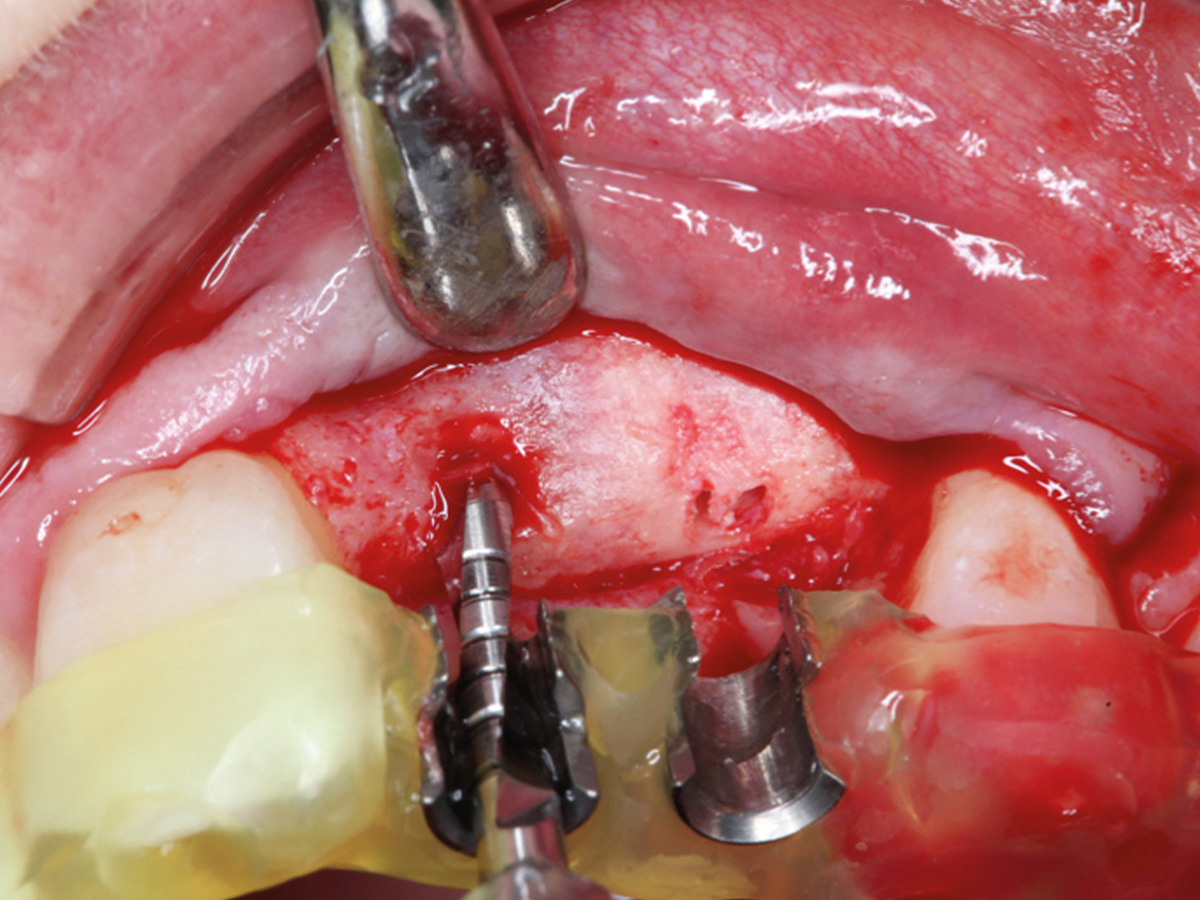

Abbildung 21

Implantation.